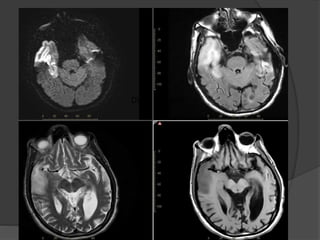

Case 5:17M, Status post cardiac arrest:

July 22

July 16

Bilateral parietal white matter diffusion restriction

and ADC hypointensity

Case 5 Diagnosis: Postanoxic leukoencephalopathy

•Uncommon syndrome (2-3%)of delayed white

matter injury after a hypoxic-ischemic injury, most

commonly due to carbon monoxide intoxication

•Period of relative clinical stability or

improvement, then acute neurologic decline,

typically 2-3 weeks after the initial insult

•DWI and conventional MRI immediately

following the insult may be normal, but reveal

confluent areas of restricted diffusion in the

cerebral white matter later

•Imaging helps in diagnosis and case

management in the acute setting and provides

information about long term prognosis

RadioGraphics 2008. Hypoxic-ischemic brain injury:Imaging findings from birth to adulthood